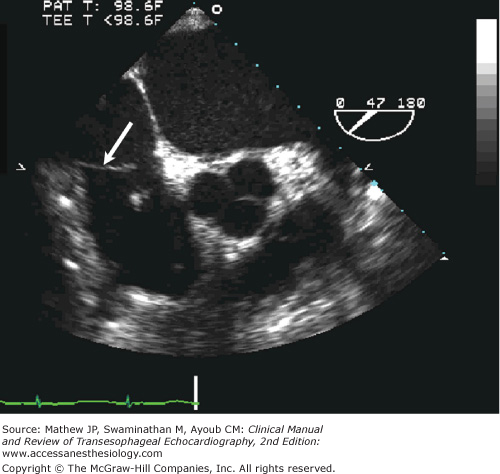

The Chiari network is a thin, mobile, membranous structure seen within the RA in multiple imaging views (Figure 3–6) that is thought to be a remnant of sinus venosus–derived structures. It is similar to but usually more extensively attached to intracardiac structures than the eustachian valve. The Chiari network is typically perforated and associated with the IVC orifice; however, the primary site of origin can vary to include the RA wall, interatrial septum, or the coronary sinus. The Chiari network moves toward the tricuspid valve during atrial contraction followed by a rapid posterior motion at the onset of ventricular systole. It has little clinical significance except that it has been associated with a patent foramen ovale, interatrial septal aneurysm, and paradoxical embolization. It is seen in 2% to 3% of all patients at autopsy and by TEE.8